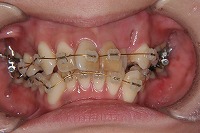

26歳1か月

正面

前歯が出ていて歯並びが悪い事を主訴に来院された、26歳1か月の女性です。診断「歯と歯槽基底の大きさの不調和による叢生」上顎は右側第1小臼歯と左側の犬歯、下顎は抜歯をせず治療を行いました。